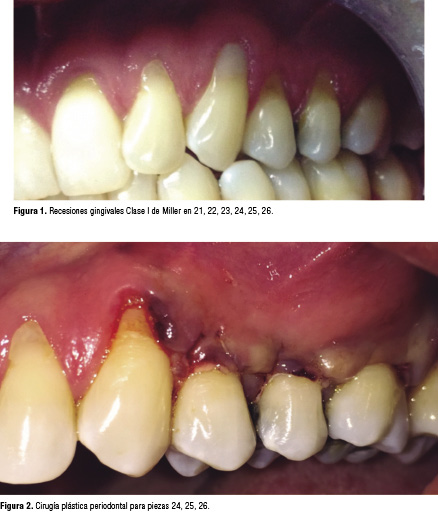

Paciente masculino, 50 años, sin antecedentes patológicos personales, se presenta a consulta por hipersensibilidad relacionadas a recesiones gingivales generalizadas principalmente en el Cuadrante II. La profundidad de sondaje y el nivel de inserción clínico pre quirúrgico se pueden ver en la Tabla 1. En la Figura 1 se puede apreciar la condición inicial del paciente.

Dentro los procedimientos pre operatorios se realizaron las instrucciones de control de placa bacteriana, un raspado supra y sub gingival y eliminación de las restauraciones Clase V desajustadas. Se realizó una primera cirugía para recubrir las piezas 24, 25 y 26 (Figura 2) y luego 3 meses después ser procedió a realizar la cirugía para las piezas 21, 22, y 23 (Figura 3).